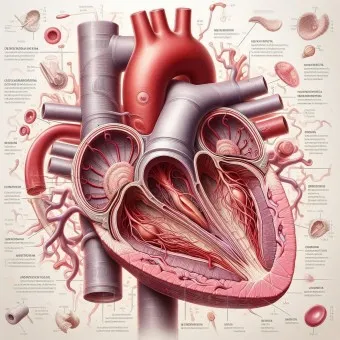

1. 심장 관련 원인

- 부정맥: 정상 심박수 범위 60-100회/분 이탈

- 심장 판막 이상: 증상 발현 시 심박수 변동 20% 이상

- 빈맥증: 휴식 시에도 심박수 100회/분 이상

- 서맥증: 심박수 60회/분 이하로 저하